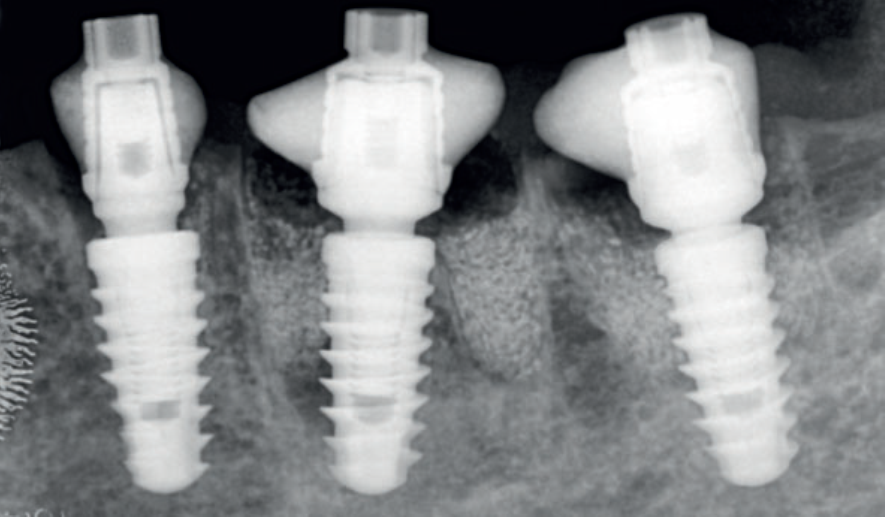

A Prótese Dentária na era digital ganhou novas perspectivas, tornando os procedimentos protéticos mais rápidos, precisos e eficazes. Entretanto, as etapas de planejamento e de transição entre a instalação dos implantes e das coroas protéticas permanecem decisivas para que os resultados almejados sejam atingidos.

A restauração protética esteticamente agradável de um implante requer a criação de um adequado perfil de emergência da mucosa peri-implantar, que é a transição entre o implante e a coroa protética. Quando corretamente explorado, proporciona uma suave transição da plataforma circular do implante para a anatomia natural do dente. Quanto mais detalhados forem estes processos, maiores serão as chances de sucesso dos tratamentos protéticos reabilitadores.

Ao serem instalados, os implantes que atingem um torque de inserção ≥ 32 Ncm podem ser imediatamente carregados com coroas unitárias de transição não oclusivas. Abaixo deste torque, ou em situações onde não desejamos correr riscos, em vez de uma coroa de transição, instala-se um cicatrizador personalizado contendo um perfil transmucoso com as mesmas características que a coroa provisória teria. Os objetivos dos cicatrizadores customizados nos casos de instalação do implante imediatamente após a exodontia são: selar o sítio cirúrgico respeitando o perfil do alvéolo de extração, estabilizar o coágulo sanguíneo e favorecer a regeneração óssea com o material substituto, evitar o colapso de tecidos moles durante o período de cicatrização e desenvolver um perfil de emergência protético ideal para a futura coroa sobre implante, baseado na anatomia do dente natural extraído, sem receber carga oclusiva.

Nos casos de instalação de implantes em regiões edêntulas, também é possível empregar cicatrizadores personalizados, desenvolvendo um perfil de emergência protético ideal para a futura coroa sobre implante, baseado na anatomia do dente natural ausente. Os dois procedimentos restabelecerão o perfil de emergência original do paciente durante a fase de cicatrização/osseointegração dos implantes, devolvendo a harmonia dentogengival, com a recuperação das papilas interdentais e a reconstituição do arco gengival côncavo, com altura adequada da margem em relação aos dentes adjacentes.

Quando corretamente indicados e executados, os cicatrizadores personalizados proporcionam bons resultados estéticos, biológicos e funcionais. A criação/manutenção de um perfil de emergência anatomicamente correto é um dos aspectos mais importantes para fornecer resultados estéticos e funcionais agradáveis às próteses implantossuportadas, tanto no setor anterior quanto no setor posterior.